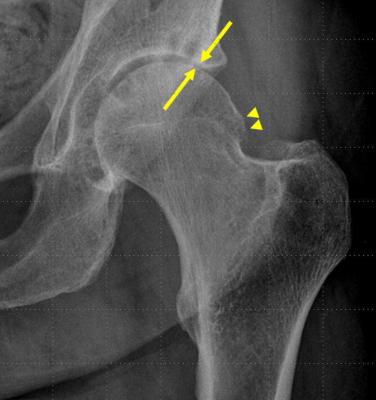

46+ Bone On Bone Hip Xray Pictures. 2 randomly places specified fake ores when a chunk. Suggest treatment for bone tuberculosis on right hip bone and leg.

Sesamoid bones are also present at the first metatarsophalangeal joint (big toe) and the first metacarpophalangeal joint (thumb). The funny bone is not really a bone.its the small spot in your elbow where the long bone of the arm meets an arm nerve.when this spot is bumped,a tingling sensation is felt that make you laugh. If you cant fit the whole long bone in the xray, which way should you position the xray? I saw my consultant today and he spoke about bone on bone whilst looking at my xray.